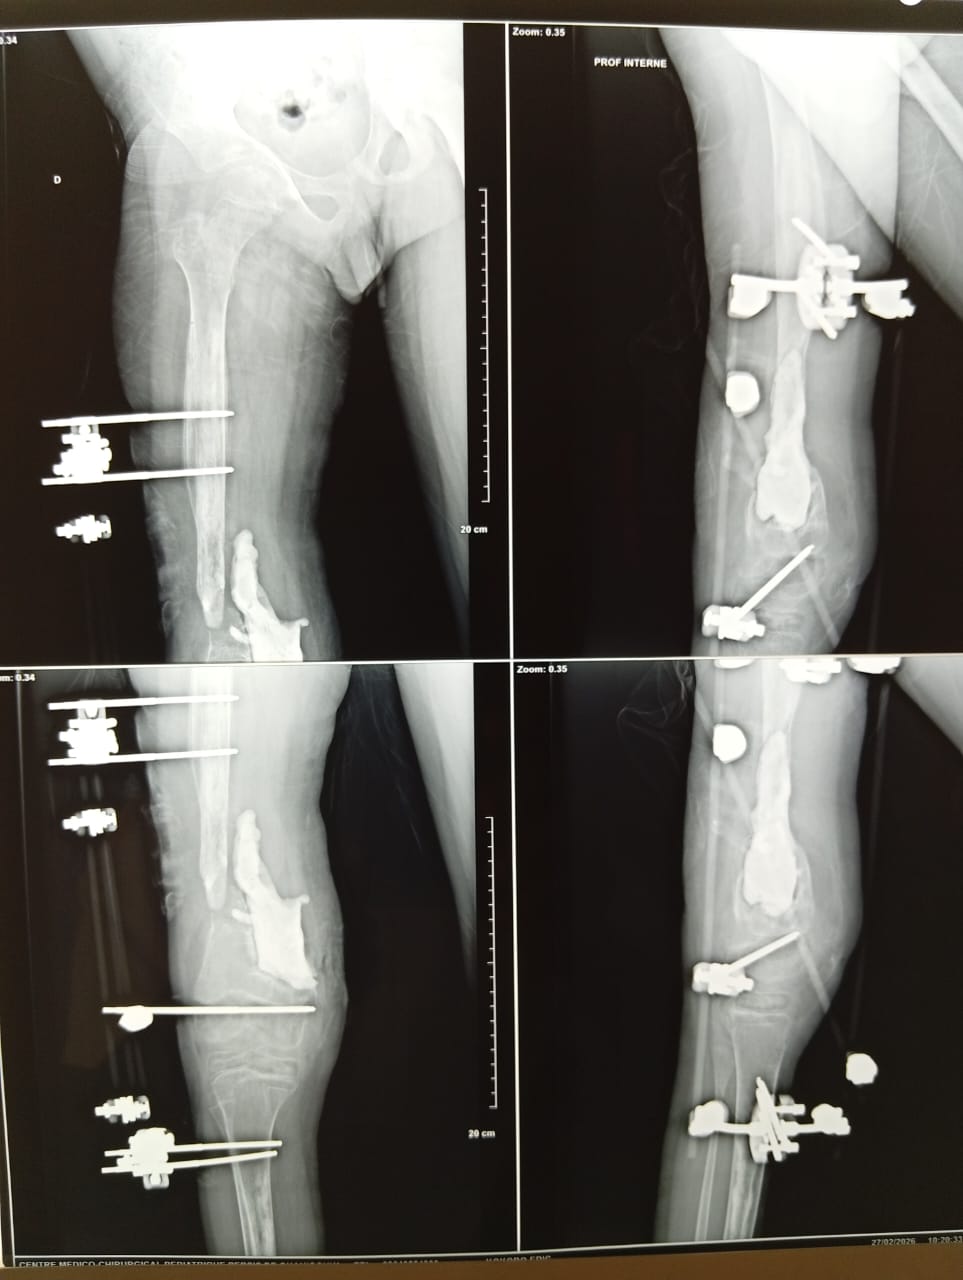

Une reprise de mission après 4 ans de pause « forcée » pour des questions de sécurité dans la zone de Ouahigouya. Un Centre magnifique que EPE a retrouvé avec tout son personnel, fidèle et engagé ! Que du bonheur. Le Dr Philippe Bédat, chef de mission, avait effectué 2 voyages « en éclaireur » en 2025. Nous avons été renforcés au niveau chirurgical par le Dr Benoi Kamaté, chirurgien pédiatrique à Bamako et qui désire se renforcer en orthopédie (il est le mari de la Dr Rokiatou Kone avec qui nous organisons les missions au Mali).

59 patients consultés et 28 opérés pour des grosses pathologies. EPE comptait 3 infirmières dont Hélène, l’épouse de notre ami Augustin, malheureusement décédé, et 2 animateurs dont un du Burkina Faso. Une équipe très efficace et sympathique…que de la joie de travailler ensemble !

Les photos sont parlantes et montrent la complexité de cette chirurgie ! Comme nous l’avons dit à notre ami Dr Bédat… »vous êtes des magiciens ». Notre admiration est grande !